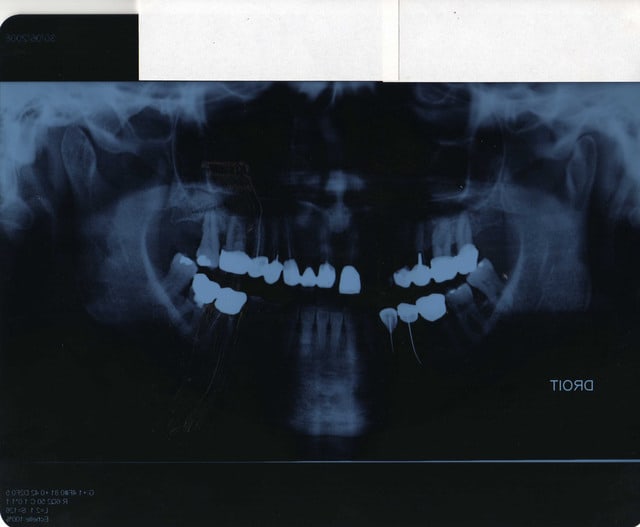

pano.....

je viens de recevoir une patiente qui va se faire poser une prothèse de hanche dans 2 mois.

Dans un temps aussi court est-ce qu'il vous parait

possible de remettre en état sans pratiquer des extractions multiples, les endos sur 15 et 47 sont pratiquement inexistantes , bridge sur dents vivantes , tout est assymptomatique, 48?